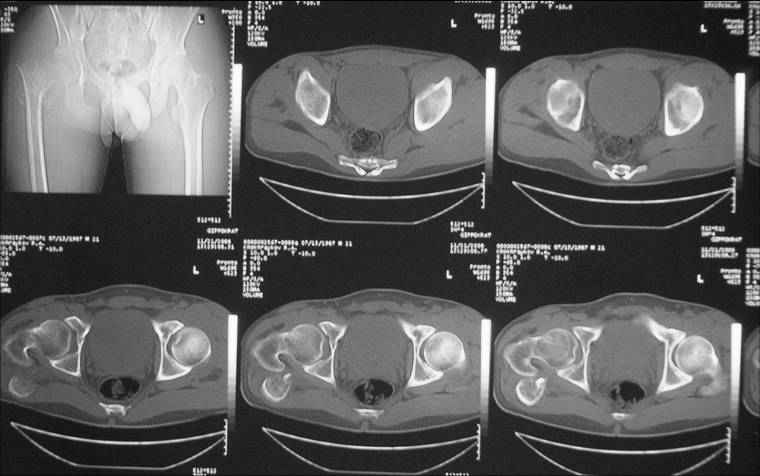

Уважаемые коллеги! Нужен совет. Больной Х., 21 год, ДЗ: ложный сустав вертельной области

правого бедра. Травма 8 мес. назад, ДТП, получил закрытый межвертельный перелом правого

бедра. Лечился в городской больнице одного из городов-спутников г. Караганды скелетным

вытяжением в течение 3 недель, затем кокситной гипсовой повязкой 2 мес.

В настоящее время имеется укорочение конечности на 7 см, умеренная

боль в вертельной области; ходит без костылей, полностью нагружая

больную конечность, при нагрузке отмечается смещение дистального

отломка проксимально примерно на 1,0 см.; объем движений в коленном

суставе сохранен; при пальпации отломков боли нет, умеренная

патологическая подвижность.